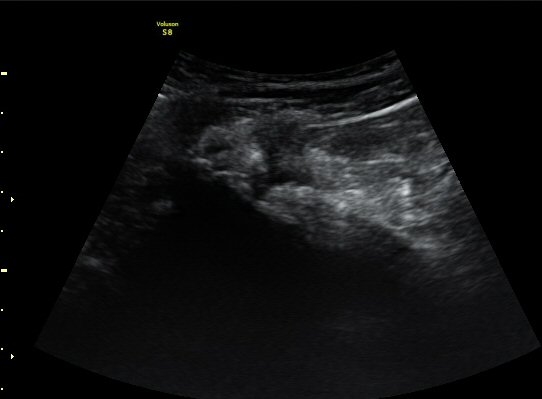

¾ûµ¢ÀÌ °üÀý Á¾´Ü¸é°Ë»ç¿¡¼­ ƯÀÌ ¼Ò°ßÀ» º¸ÀÌÁö ¾ÊÀ½(»çÁø 1).

ŽÃËÀÚ¸¦ ¾ûµ¢ÀÌ °üÀý ¿ÜÃø Á¾´Ü¸é°Ë»ç ½Ã ÀüÇÏÀ屨(AIIS)¿¡¼­ ¼®È¸È­¼º À½¿µÀÌ °üÂûµÊ(»çÁø 2, 3).